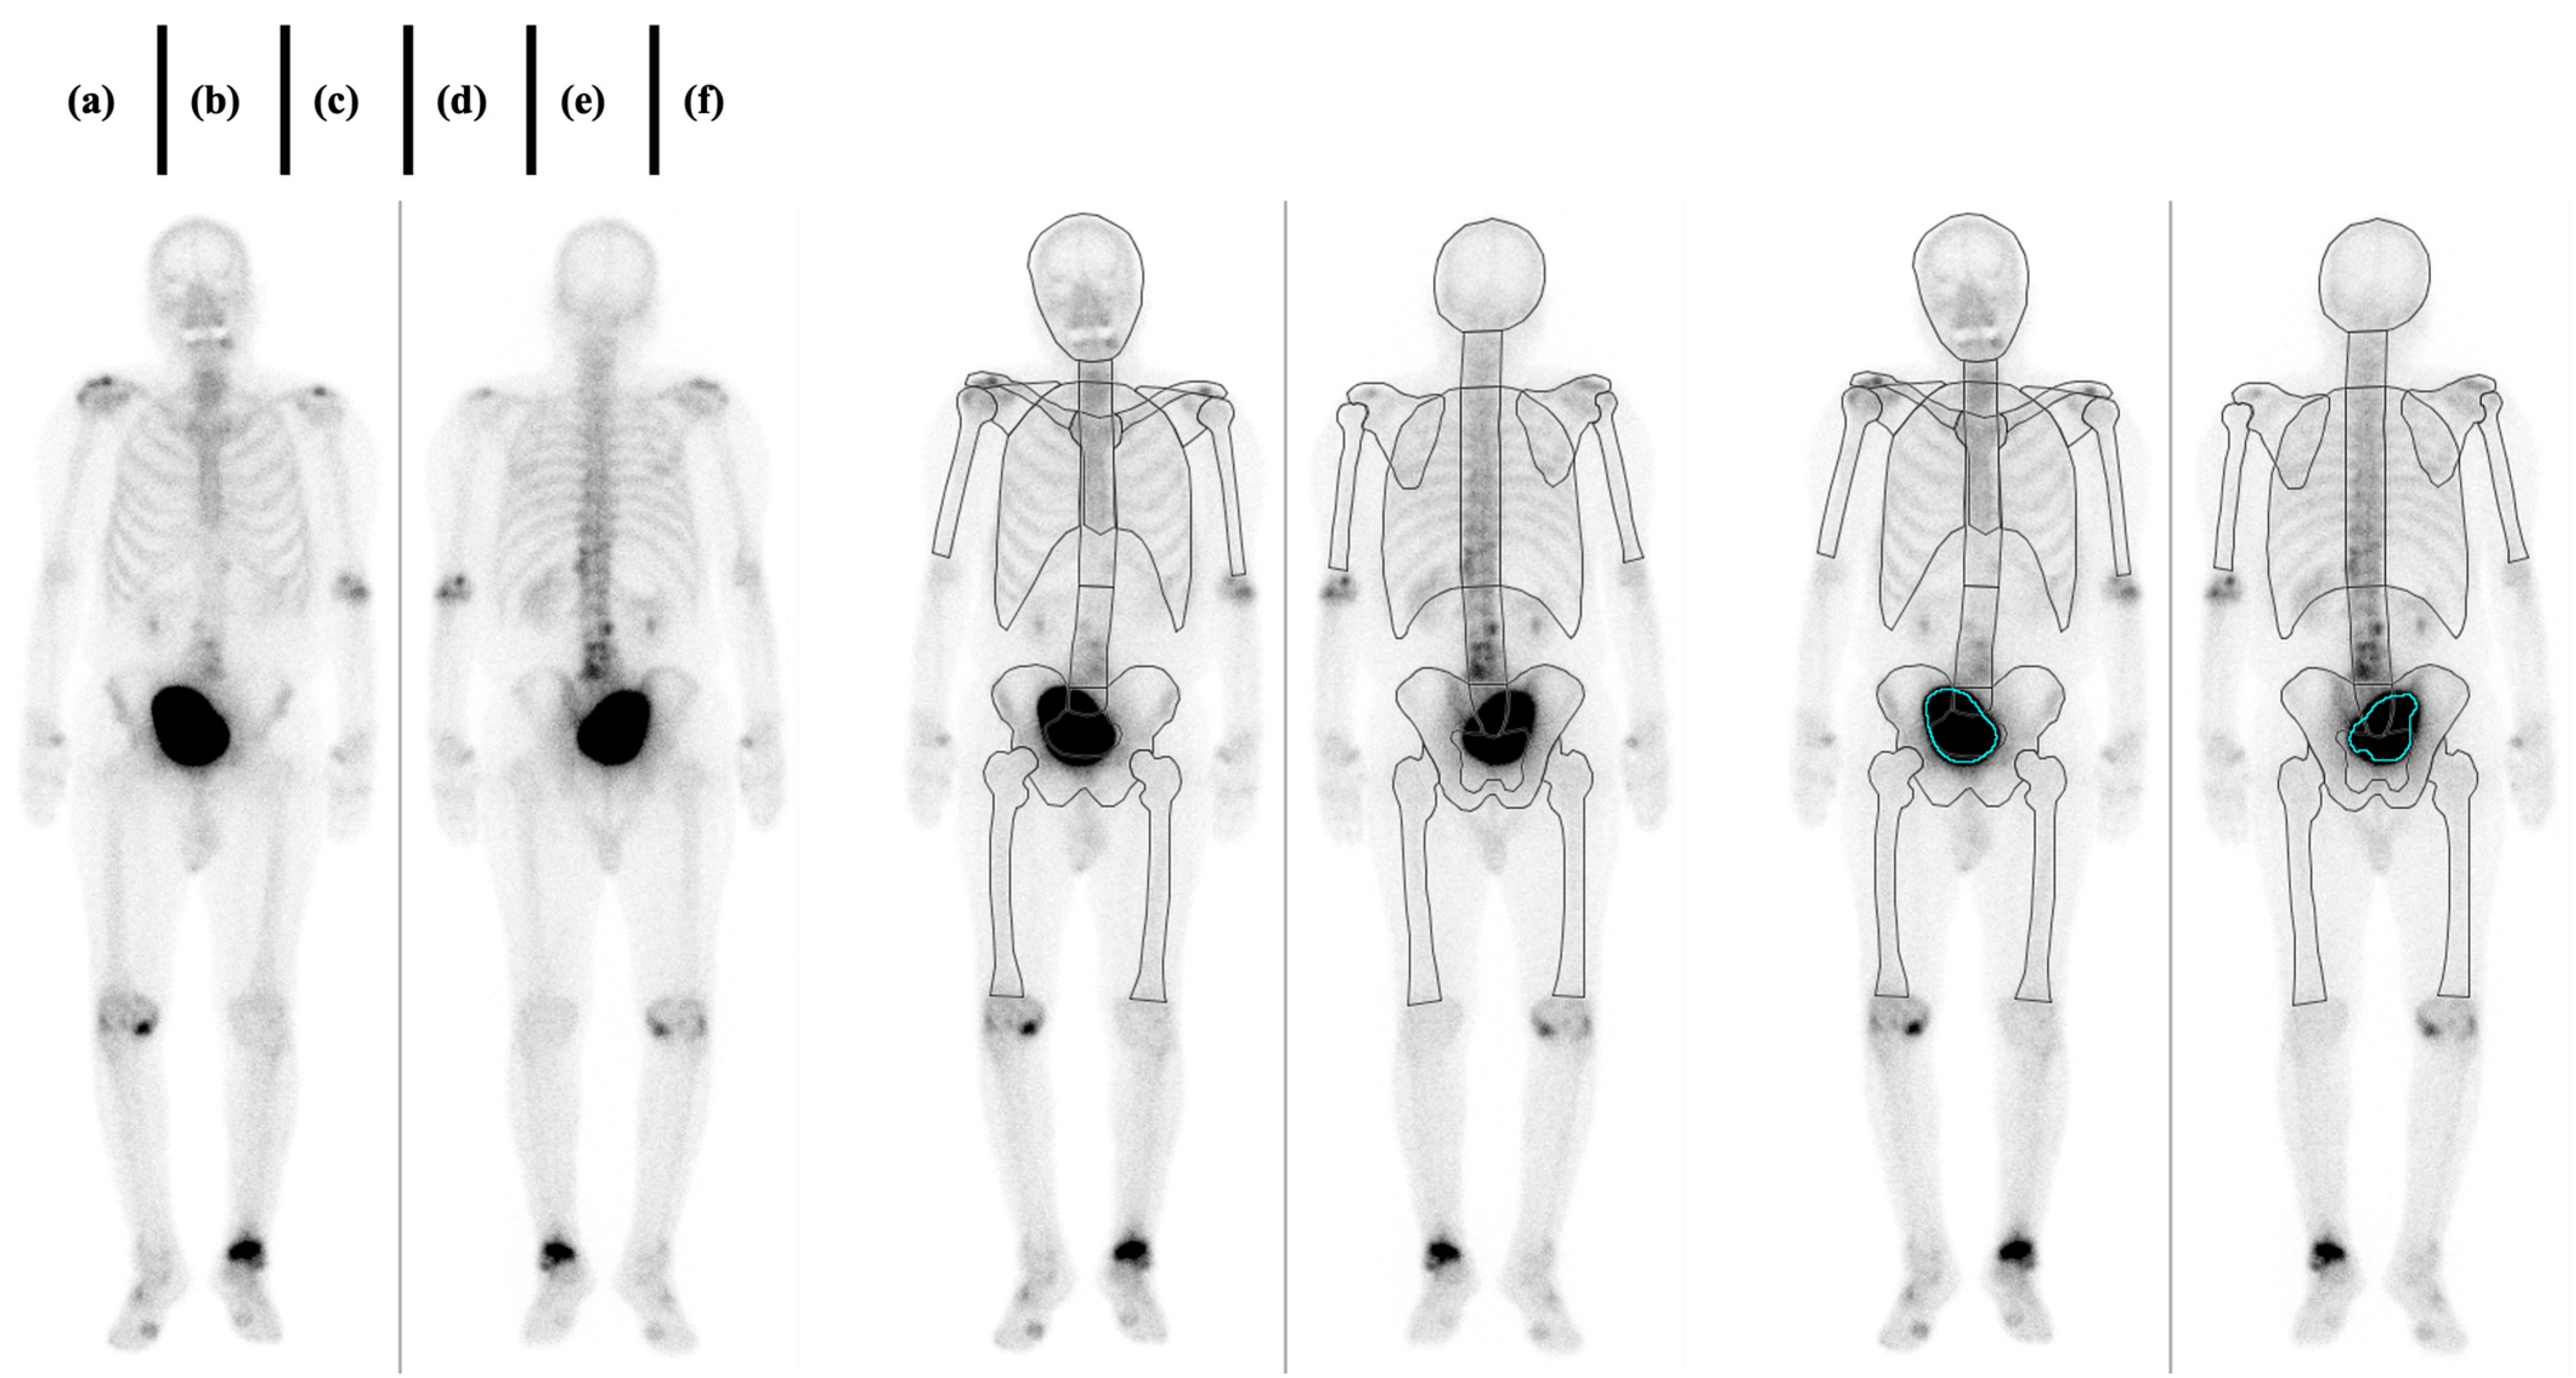

2.3. Imaging